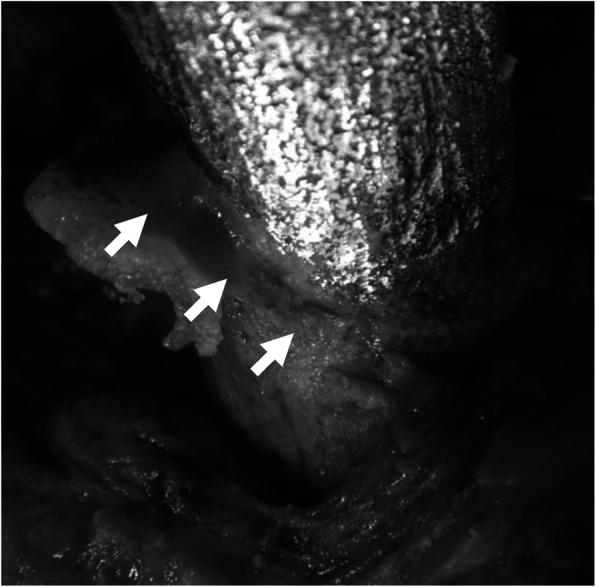

Another rationale for retaining well-fixed stems is that bone ingrowth is thought to function as a barrier to microbial invasion. Today, almost all cementless stems are circumferentially-porous coated over the proximal portion. This makes the removal of well-fixed stems difficult; however, circumferential bone ingrowth may function as a barrier against intramedullary invasion of bacteria. The surgeon should carefully examine the entire circumference of the bone-implant interface and perform thorough debridement using tools such as a high-speed burr until fresh, clean bone ingrowth can be identified (Fig. 3). Possibility of stem retention could be increased when this aggressive and circumferential debridement of bone-implant interface is combined with a thorough debridement of the entire synovial capsule. Successful retention of a well-fixed stem could reduce both local and systemic burden on patients, enabling preservation of hip function between the two-stage surgeries, which could contribute to the accomplishment of ultimate goal of long-term clinical success.

Fig. 3.

Intraoperative findings of the Case 1; Thorough debridement of the proximal femur was performed using a high-speed burr until fresh, clean bone ingrowth was identified circumferentially